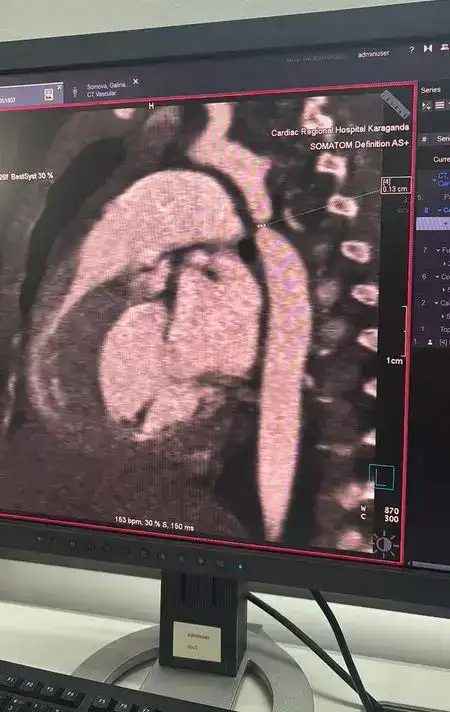

В Караганде была успешно проведена операция на сердце трёхмесячной девочке, страдающей от критической коарктации аорты. Этот врождённый порок сердца был обнаружен во время госпитализации ребёнка с пневмонией в многопрофильную больницу №1. Врачи, проводя обследование, выявили серьёзную патологию, после чего девочку экстренно перевели в Кардиоцентр.

Команда кардиохирургов из Караганды и ведущие специалисты из Астаны, включая кардиохирурга Галымжана Утегенова и анестезиолога Хафиза Ахмерова, провели операцию в рамках мастер-класса. Процедура длилась почти пять часов и включала резекцию коарктации аорты с наложением анастомоза "конец в конец". В ходе операции также была обнаружена открытая артериальная протока, которая была успешно легирована.